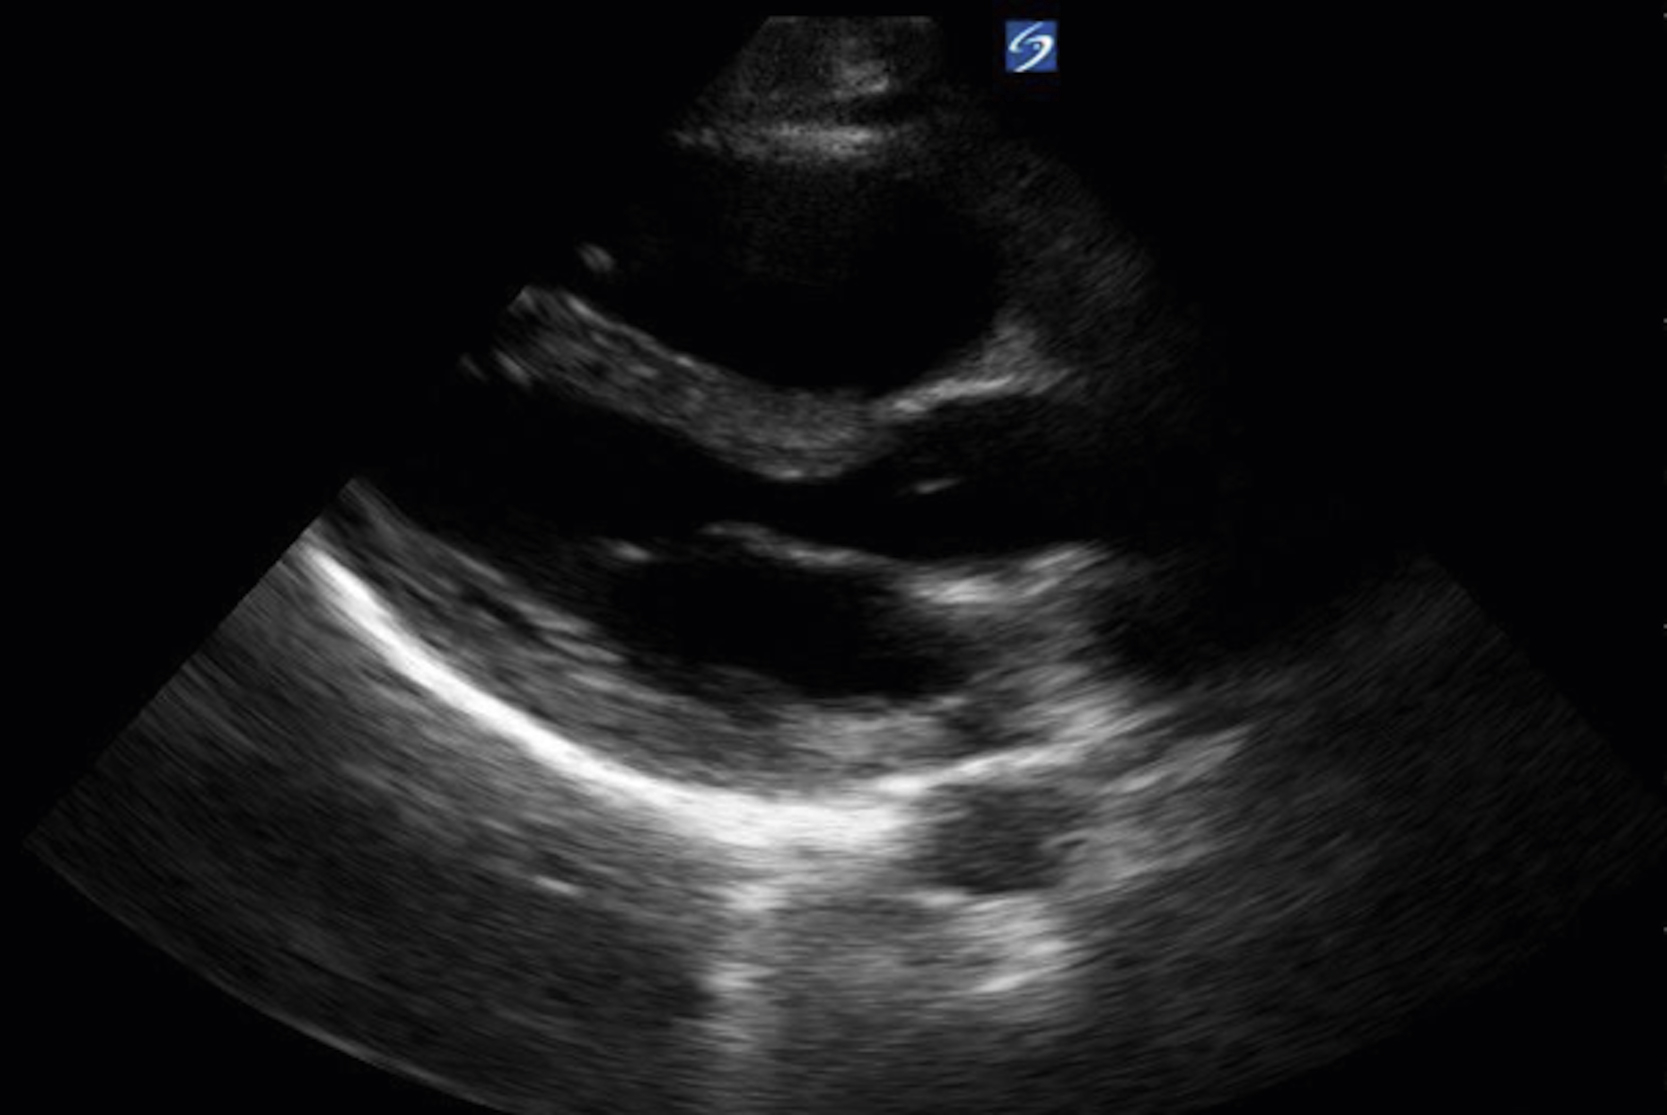

RV assessment is another useful tool for the emergency clinician when pulmonary embolism (PE) is high on the differential. With increasing right heart pressure, the RV dilates, squeezes poorly, and ultimately develops flattening of the interventricular septum, creating the “D” sign ( Figs. e3.12, e3.13 , and Video e3.11 ). The sparing of the RV apex is called the McConnell sign and is highly suggestive of PE. ,

Apical 4-chamber view of the heart with an enlarged RV.

Parasternal short axis view with “D” sign signifying increased RV pressure.